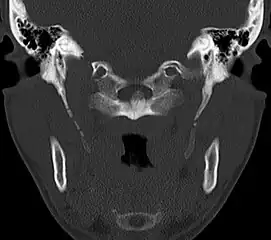

CT scan, coronal section showing bilateral extended styloid process and stylohyoid ligament ossification (incidental finding) -

Imaging is important and is diagnostic. Visualizing the styloid process on a CT scan with 3D reconstruction is the suggested imaging technique.[11] The enlarged styloid may be visible on an orthopantogram or a lateral soft tissue X ray of the neck.